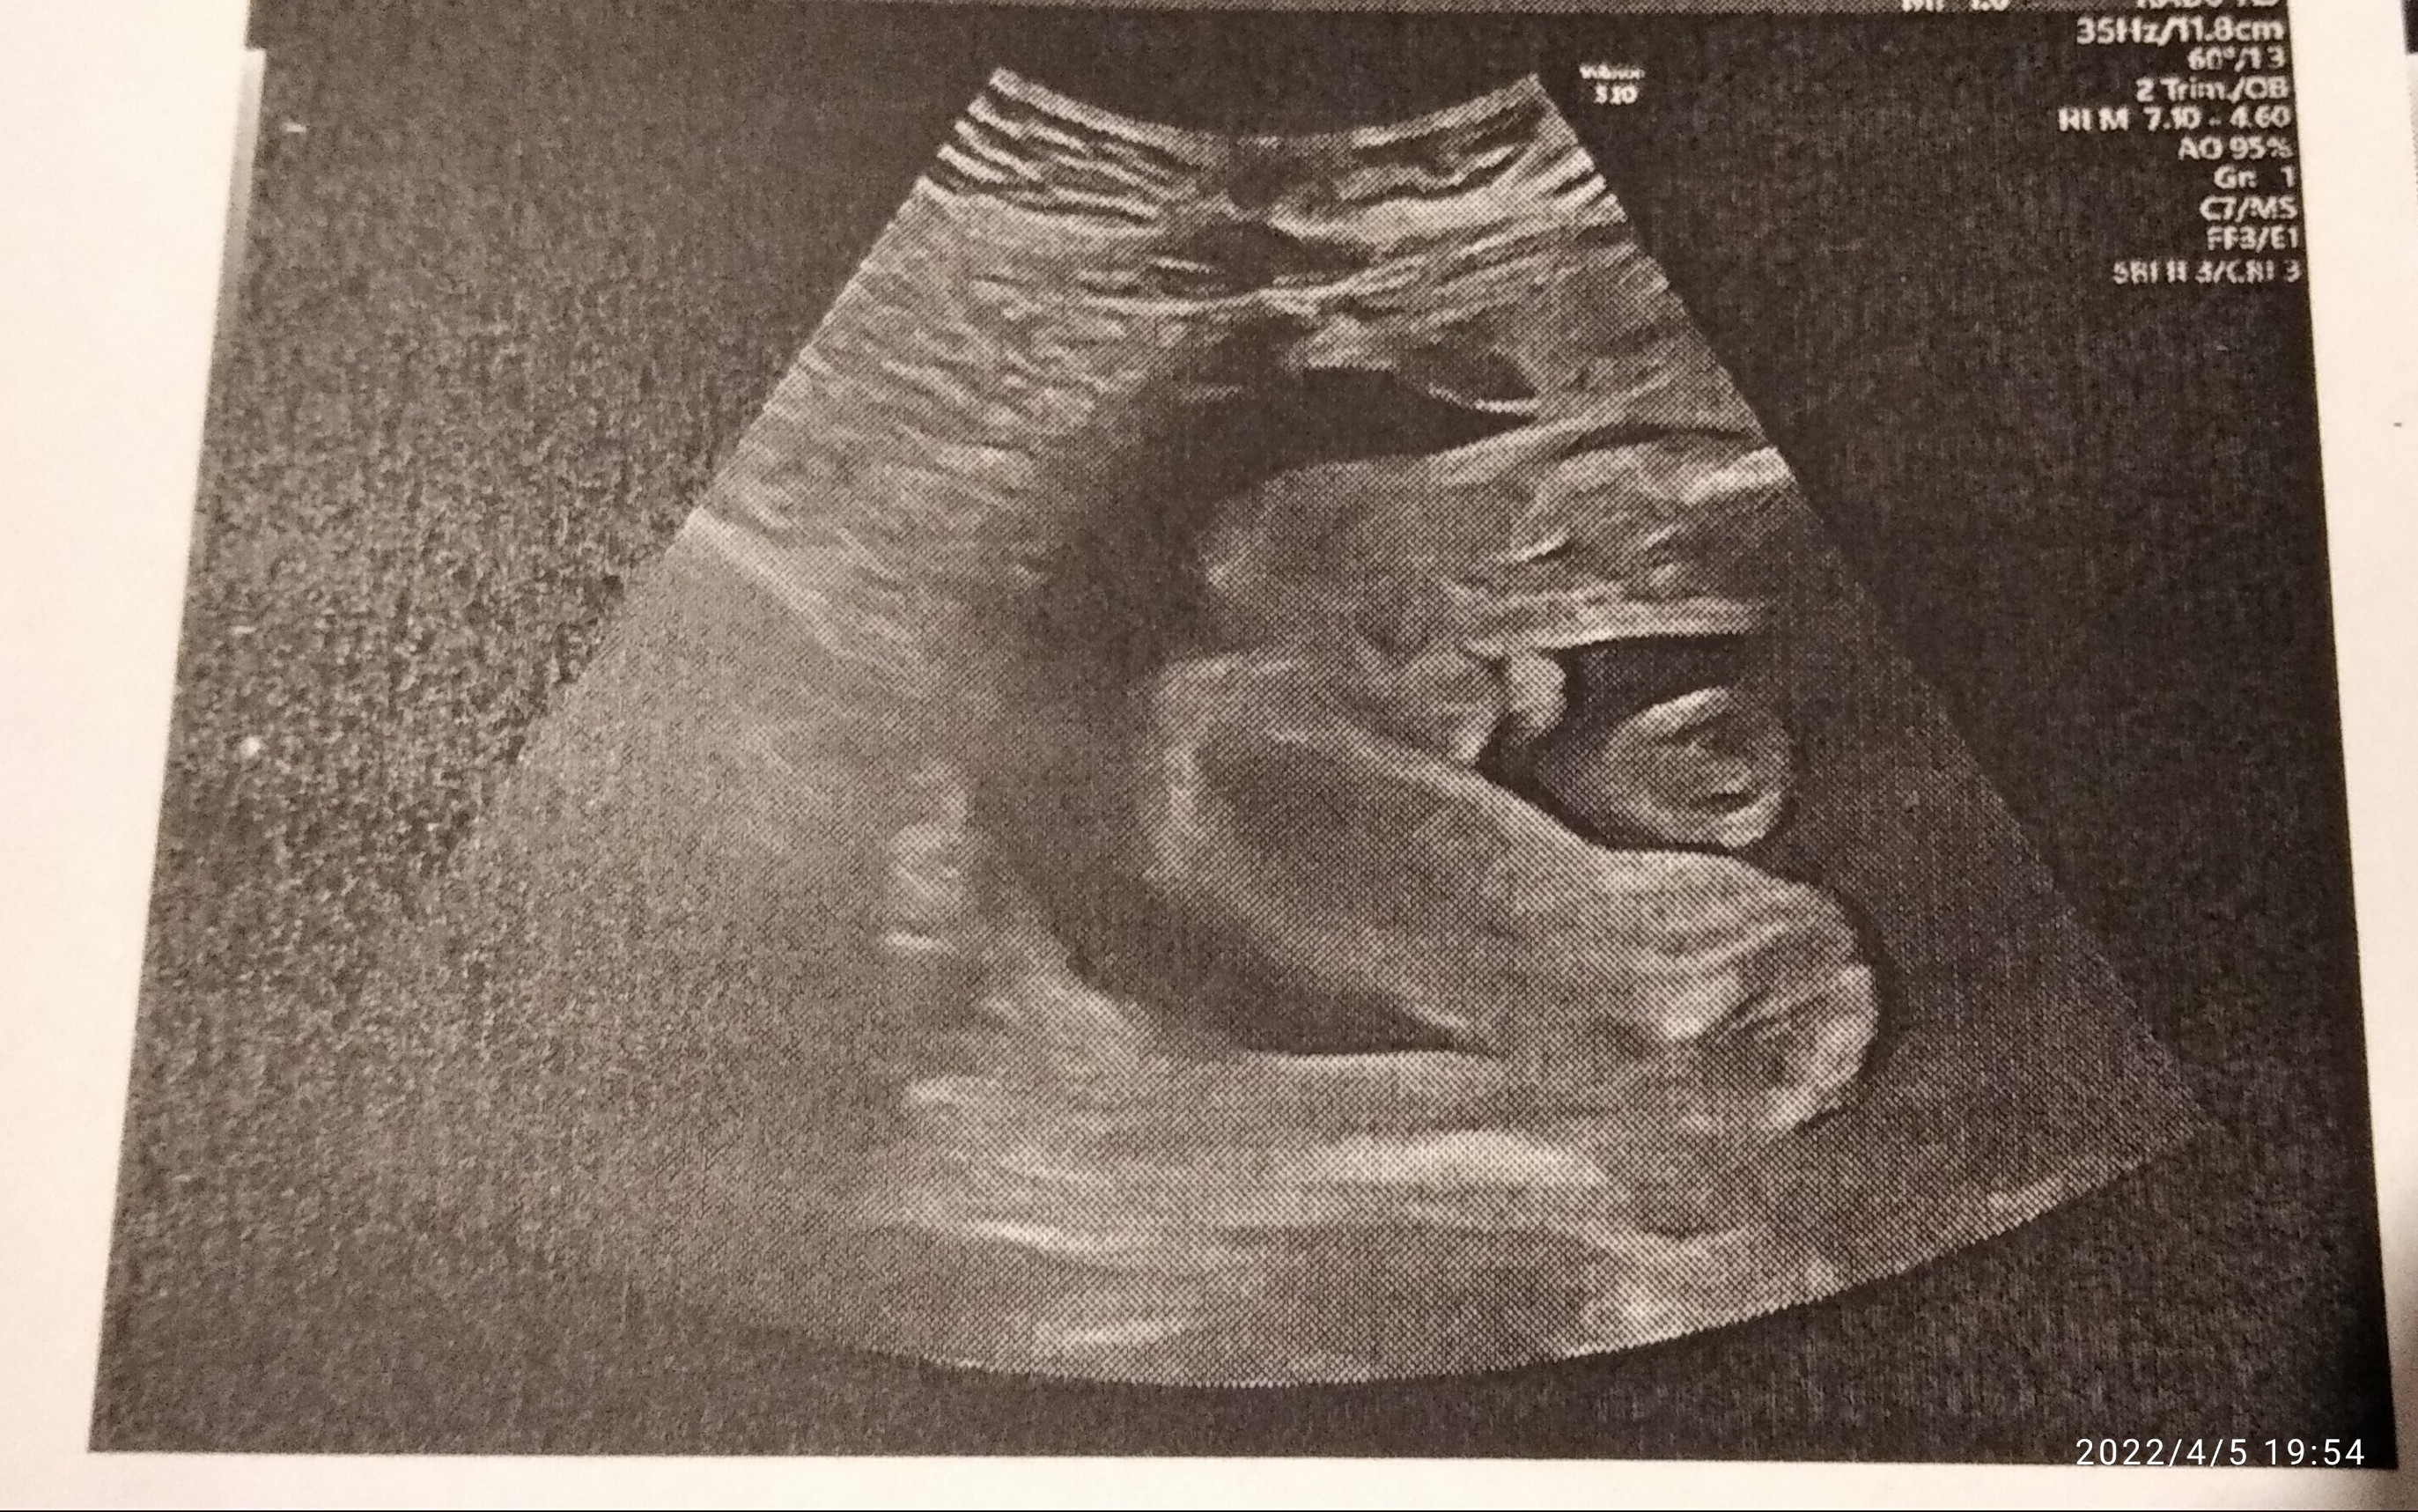

Tydzień ciąży, co widzicie drogie Panie chłopca czy dziewczynkę?

Wydaje mi się, że wygląda to w ten sposób jak zaznaczyłam na zdjęciu niżej. Może są tutaj bardziej doświadczone mamy niż ja i się wypowiedzą. Jedną córkę mam, teraz fajnie by było mieć chłopca ☺

Ok, No zobaczymy co się urodzi za ok 8 tygodni. Zastanawia mnie ta ciemna kropka w kroku.Witam, według mnie dziewczynka.

Pokaże Ci jak wygląda zdjęcie mojego dzidziusia z tej perspektywy, mam mieć synaOk, No zobaczymy co się urodzi za ok 8 tygodni. Zastanawia mnie ta ciemna kropka w kroku.

Nie mam innego zdjęcia, lekarz stwierdził ze chłopiec. Ze ta cześć koło dupki to worek mosznowy. No ale ta kropka mnie zastanawia No i nie widzę wystającego penisa. Ważne żeby się urodziło zdrowe. Synek czy dziewczynka bez różnicy.Też mnie to zastanawia, może masz inne zdjęcie? Lekarz nic nie mówił?

Według miesiączki 23, a według USG 24A który to tydzień u Ciebie?